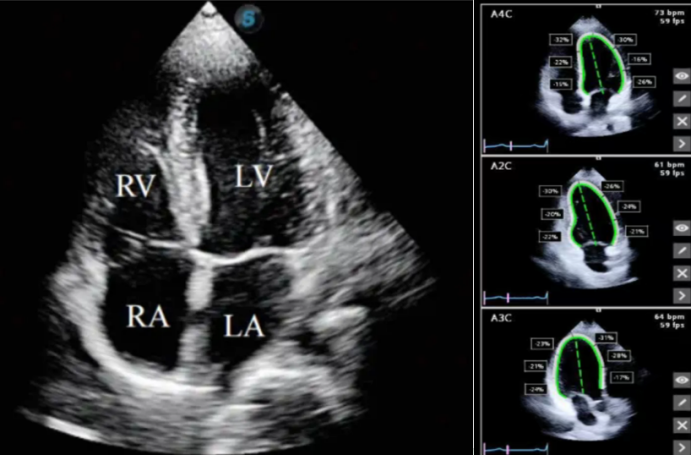

在组织分割中,AI可自动标注超声图像中的精细结构。图2左为左前臂普通超声图像,因结构显示缺乏直观标识,难以直接分辨具体解剖部位。借助AI超声技术处理后,呈现为图2右所示图像,AI可对肌肉、神经、血管等不同解剖结构进行精准标识区分。这种AI辅助超声的模式,在未来肌肉、脏器相关检查及穿刺操作等场景中(图3),有望为临床提供更清晰、直观且具精准解剖指引的超声成像表现,助力提升诊疗操作的准确性与效率。

图片

3  AI辅助描记心脏位置